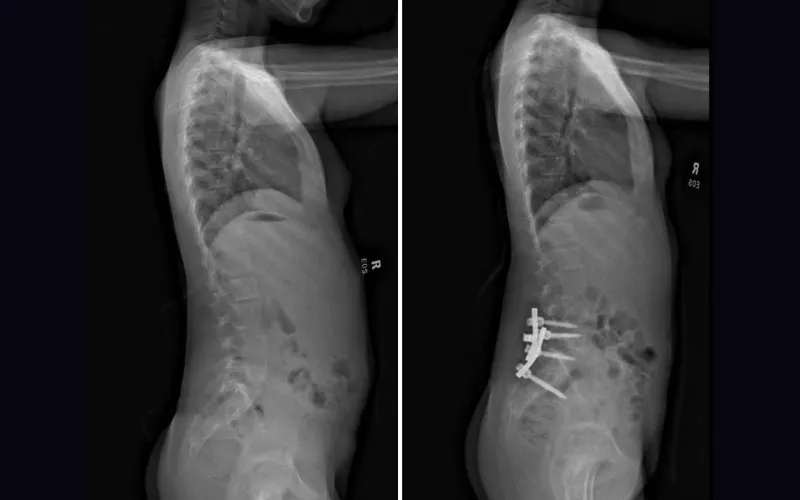

Images showing the spine of a patient before and after surgery.

Dr. Vitale and Dr. Oh collaborated on a surgery to correct progressive congenital scoliosis with a L5 hemivertebra. Together, they performed a hemivertebrectomy and posterior spinal fusion to remove the vertebra and correct the patient’s spinal alignment.

Dr. Vitale and Dr. Oh recently completed a complex case together, successfully performing a hemivertebrectomy and posterior spinal fusion in an 11-year-old with progressive congenital scoliosis with a L5 hemivertebra. The hemivertebra, which caused 70 degrees of scoliosis, needed to be excised and the spine fused, so Dr. Vitale and Dr. Oh devised a surgical plan that involved Dr. Oh performing the hemivertebrectomy and Dr. Vitale performing the spinal fusion.

The procedure was successful; the patient has experienced dramatic improvement in her spinal alignment and deformity and has resumed her normal activities, including gymnastics.